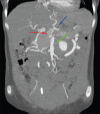

Dacron graft aneurysm with dissection

Dacron grafts have been used as a conduit for large caliber arteries for many years successfully. However, these grafts can undergo complications such as aneurysm formation, rupture, and failure. Evaluation of these complications are of paramount importance because of its tendency to rupture and cause death. Imaging plays an important role in identifying and monitoring of these complications, and also provides a road map to the vascular surgeons for early intervention and revascularization.